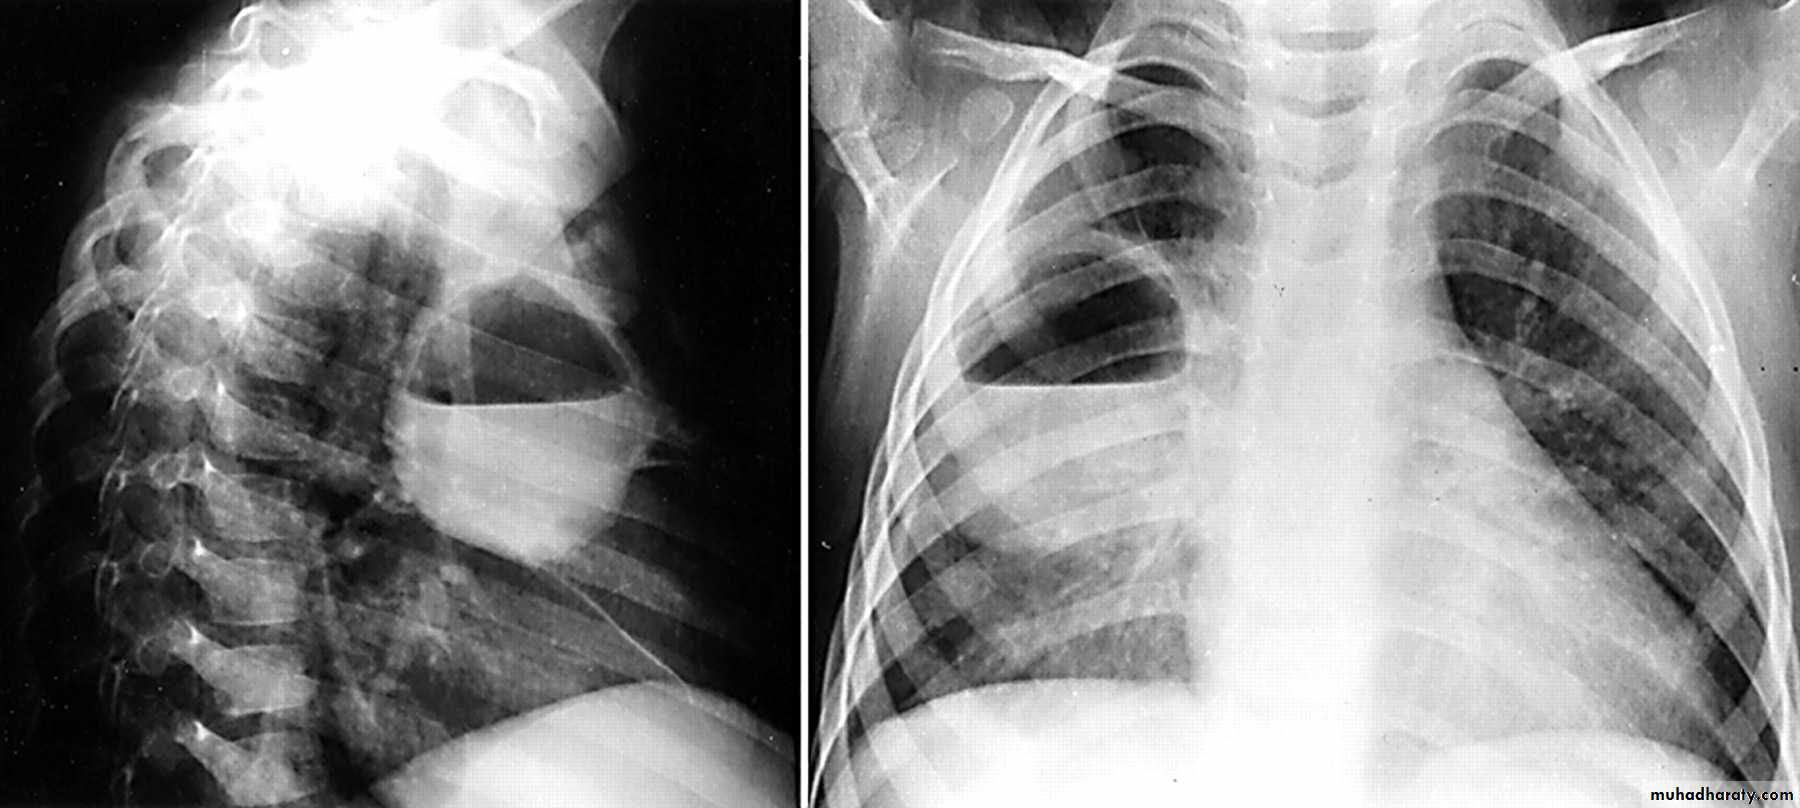

61.post primary TB notice upper apical Broncho pneumonic shadow

Bilateral Patchy opacification of the lungs involving upper zones, a cavity can be seen in the right uper lobe( 3rd photo)bronchopnemonia

Bilateral patchy opacity mainly involving lower lung zonesprimary TB bronchopnemonia

Bilateral patchy opacity mainly involving upper lung zonesBoth of them have similar appearance of broncho pneumonic shadow